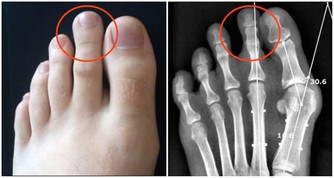

消化道出血或惡性腫瘤:消化道出血時,血液在患者的腸道中聚集。胃酸及腸道細菌將血液分解後,排出的屁有腥臭味。患腸道惡性腫瘤時,癌組織糜爛、出血,再加上細菌的分解發酵作用,也會使放出的屁有腥臭味。

腸道細菌感染:腸道內的細菌毒素通常可使腸黏膜遭到破壞,黏膜上皮細胞壞死並脫落,經過發酵之後,這些物質可產生惡臭氣體,並隨屁一起排出。

若屁奇臭難聞,可能有消化道出血、菌痢、阿米巴痢疾、潰瘍性結腸炎、出血性小腸炎等炎症。此外,惡性腫瘤晚期,因癌腫組織糜爛,蛋白質腐敗,由於細菌的作用,放出的屁也會很臭。愛放屁且經常放臭屁的人就有可能患上大腸疾病,這時你就需要前去診斷了。

如果消化道出血時, 血液在腸腔內滯積, 或腸道發生炎症、潰瘍時, 排出的氣體往往比較腥臭,最好找醫生進行診治,這可能是罹患胃腸道腫瘤的警訊。當患有腸道惡性腫瘤時, 由於癌腫組織糜爛,, 蛋白質腐敗, 經肛門排出的氣體也可出現腐肉樣奇臭。